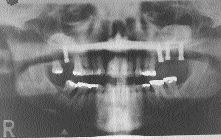

Pre-Implant Bone Manipulation for the General Practitioner

FIGURE 41--Implants have been placed without complication into the newly formed bone/graft material where they were intended to be from the prosthetic design.

In a great many of the cases that cross my desk for implant consultation, the teeth that are going to be replaced with implants have either: 1. been missing for a substantial period of time, or 2. have recently been extracted by a ‘what ever it takes’ style of dentistry in which the labial bone … Read more